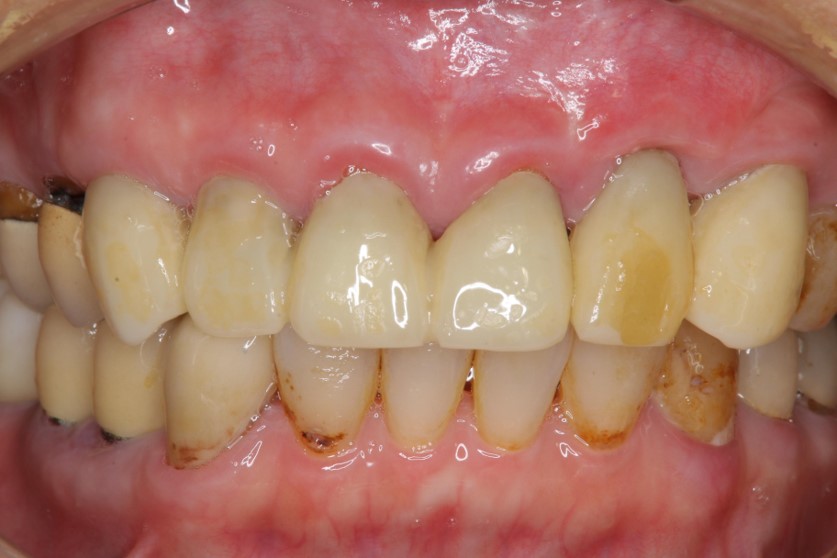

治療後,咬合牙周適應良好

治療後,密合度良好